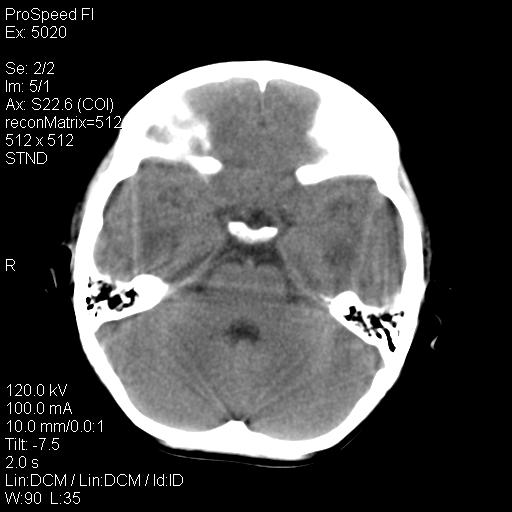

标题: PED1637:M 6Y 顶部无痛性包块两月。 [打印本页]

标题: PED1637:M 6Y 顶部无痛性包块两月。

考虑嗜酸性肉芽肿

支持点:

1、年龄--6岁

2、颅骨局部缺失,边缘光滑、整齐

嗜酸性肉芽肿是郎罕氏细胞增多症的一种表现,以前称为组织细胞增多症x。嗜酸性肉芽肿多发生于5-10岁的儿童,侵犯部位为骨骼和肺。

嗜酸性肉芽肿的临床表现为:局部疼痛、肿胀,血沉升高。

颅骨的病损表现为内外颅骨板层不规则的锋利的破坏,形成“斜边缘”,有一定的特点

颅骨为好发部位,生长缓慢,常位于顶骨、枕骨及颞骨,表现为颅骨缺损,呈圆形或椭圆形,边界清,无硬化

事发冠状缝与矢状缝交界区,密度较低,考虑表皮样囊肿可能性大,其次不除外嗜酸性肉芽肿